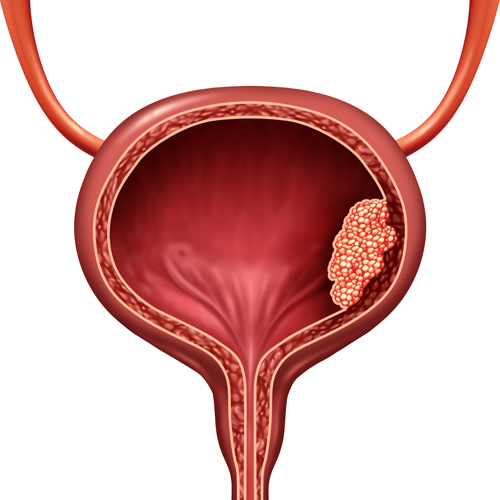

A bladder is the hollow organ in that pelvis that stores urine before it leaves the body. Urine is made by the kidneys and then carries to the bladder through ureters (tubes), and when you urinate the muscles in bladder contracts and urine is forced out of the bladder through the urethra. Bladder cancer occurs when the cells in the urinary bladder start to grow uncontrollably. As more cancer cells develop, they start forming tumours and spread to other parts of the body.

In most cases, bladder cancer starts in the innermost lining of the bladder – called the urothelium or transitional epithelium. As the cancer grows through these layers in the bladder wall, it becomes advanced, making it harder to treat. Over time the cancer can spread to other parts of the body such as distant lymph nodes, the bones, the lungs and the liver.